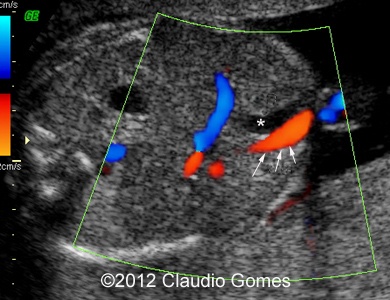

Images 6, 7: 37 weeks, four-chamber and five-chamber view with the aorta and Azygos vein

f3

Fig7

Images 8-11: Persistent right umbilical vein and Inferior vena cava interruption with continuity of the flow via Azygos vein on grayscale and color Doppler